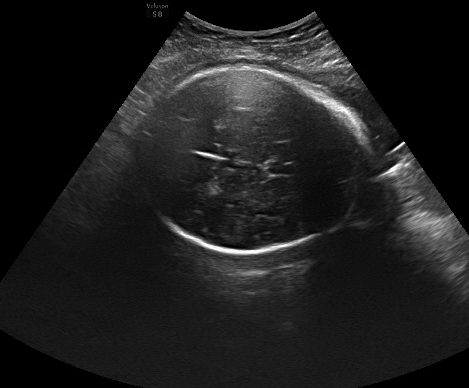

TABLE I: Sample outputs comparing reference captions with captions generated by the proposed model.

Uterine Ultrasound Image Reference Caption Generated Caption

[Uncaptioned image] a large slightly oval circle that represents the cranial contour of the fetus inside it is possible to see the cavum of the septum pellucidum on the right only but it is possible to calculate the biparietal diameter a large slightly oval circle that represents the cranial contour of the fetus the cavum of the septum pellucidum can be seen on the right it is possible to calculate the biparietal diameter

Consequently, the CNN-BiGRU model outperformed the other baseline models regarding BLEU and ROUGE scores and demonstrated lower loss values, underscoring its effectiveness in this application. Moreover, Table I provides further evidence by illustrating sample outputs that compare reference captions with captions generated by the CNN-BiGRU model. This comparison vividly showcases the model’s ability to generate high-quality captions through its robust bidirectional processing capabilities.